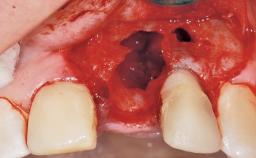

Late Flapless Placement of an Implant in a Maxillary Left Central Incisor Site

Bone Augmentation Horizontal|Staged

Bone Volume Deficient horizontally, requiring prior grafting